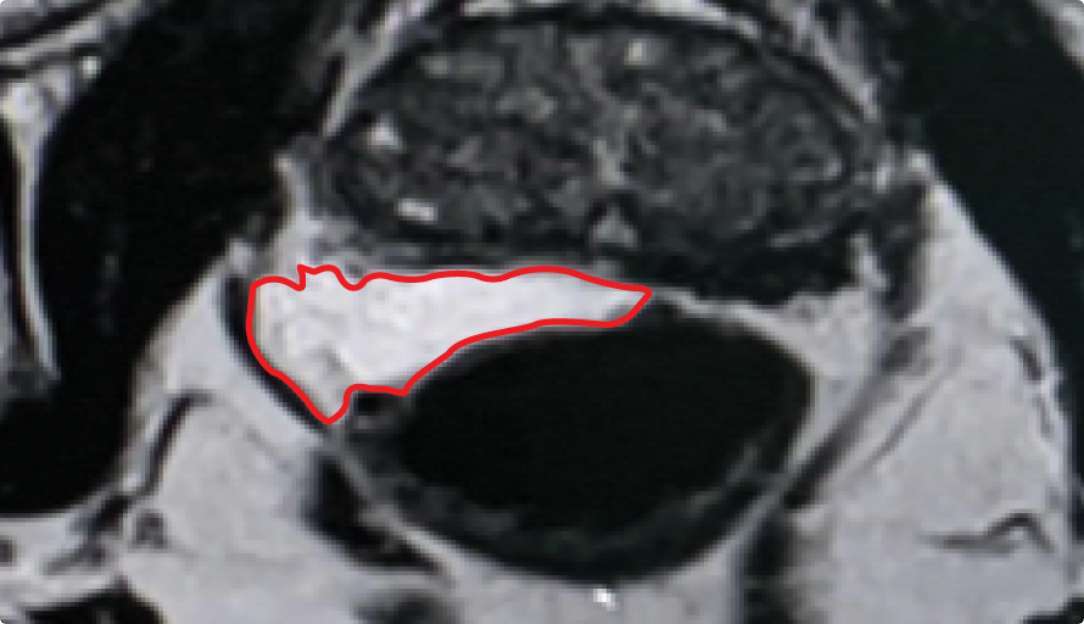

Implant Symmetry RESULTS6 >95%

Pivotal Trial Patients; % of implants centered on prostate midline

PEG HYDROGEL

Implant Symmetry RESULTS7 >49%

First Barrigel Cases - Consecutive Patients (Same Day)

TRUS images courtesy of Daniel R. Welchons, MD

Urologist; New York, United States